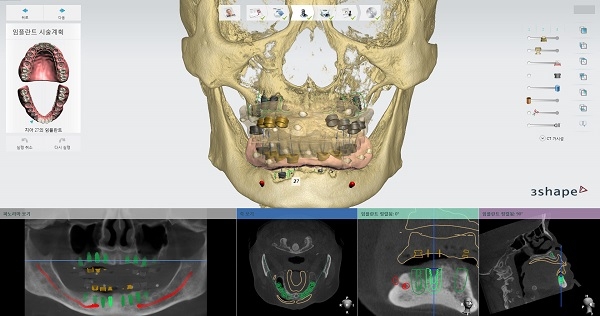

선치과 병원은 가장 먼저 임플란트 식립 전 검사 단계에서 3D구강스캐너와 치과CT(Cone Beam CT)로 환자의 구강 상태를 정밀하게 진단해 구강 구조와 턱뼈, 피부 밑 신경의 상태까지 확인한다는 것. 골밀도가 낮은 곳에 임플란트를 심거나 신경선을 잘못 건드리면 수술이 실패하거나 신경손상 같은 부작용이 발생할 수 있기 때문이다.

위의 장비들을 통해 얻은 3차원 정보는 즉시 컴퓨터로 전송돼 수술을 가장 안전하고 성공적으로 마칠 수 있도록 ‘모의수술’ 단계를 거치게 된다. 특히 이 모의수술 단계에서 최종보철물이 제작되며, 이에 따라 임플란트 식립 기간도 6개월에서 1일로 크게 줄게 된다는 것이다. 예전에는 임시치아를 수술 당일에 끼우고 수개월 뒤 다시 내원해 최종보철물로 교체했다고 한다.